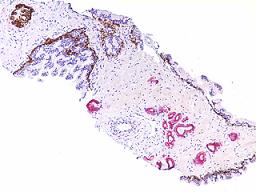

The Genitourinary (GU) pathology service at UMass Memorial  Medical Center provides skilled interpretation of specimens from the prostate, urinary bladder, kidney and testis.   Our GU Genitourinary Imagepathology section serves the UMass Memorial Medical Center and urology practices in Massachusetts and Connecticut.  We have developed a novel molecular diagnostic technique combining cytology and fluorescent in situ hybridization (FISH) analysis, a cutting edge technology for the diagnosis of urothelial carcinoma. We utilize an array of immunohistochemical and molecular biological techniques in the evaluation of  pathological diagnostic problems.

Genitourinary ImageOur major research focus is the identification and validating novel biomarkers for diagnostic and prognostic use. Alpha-methylacyl-coenzyme A racemase (AMACR/P504S), a molecular diagnostic biomarker for prostate cancer that Dr. Jiang first described in 2001, now assists pathologists around the world accurately diagnose prostate cancer in prostate needle biopsies.  Recently, we discovered IMP3, a new molecular marker that allows patients and cliniciansget an accurate prediction of the metastatic potential or progression of renal cell carcinoma and superficial bladder cancer.